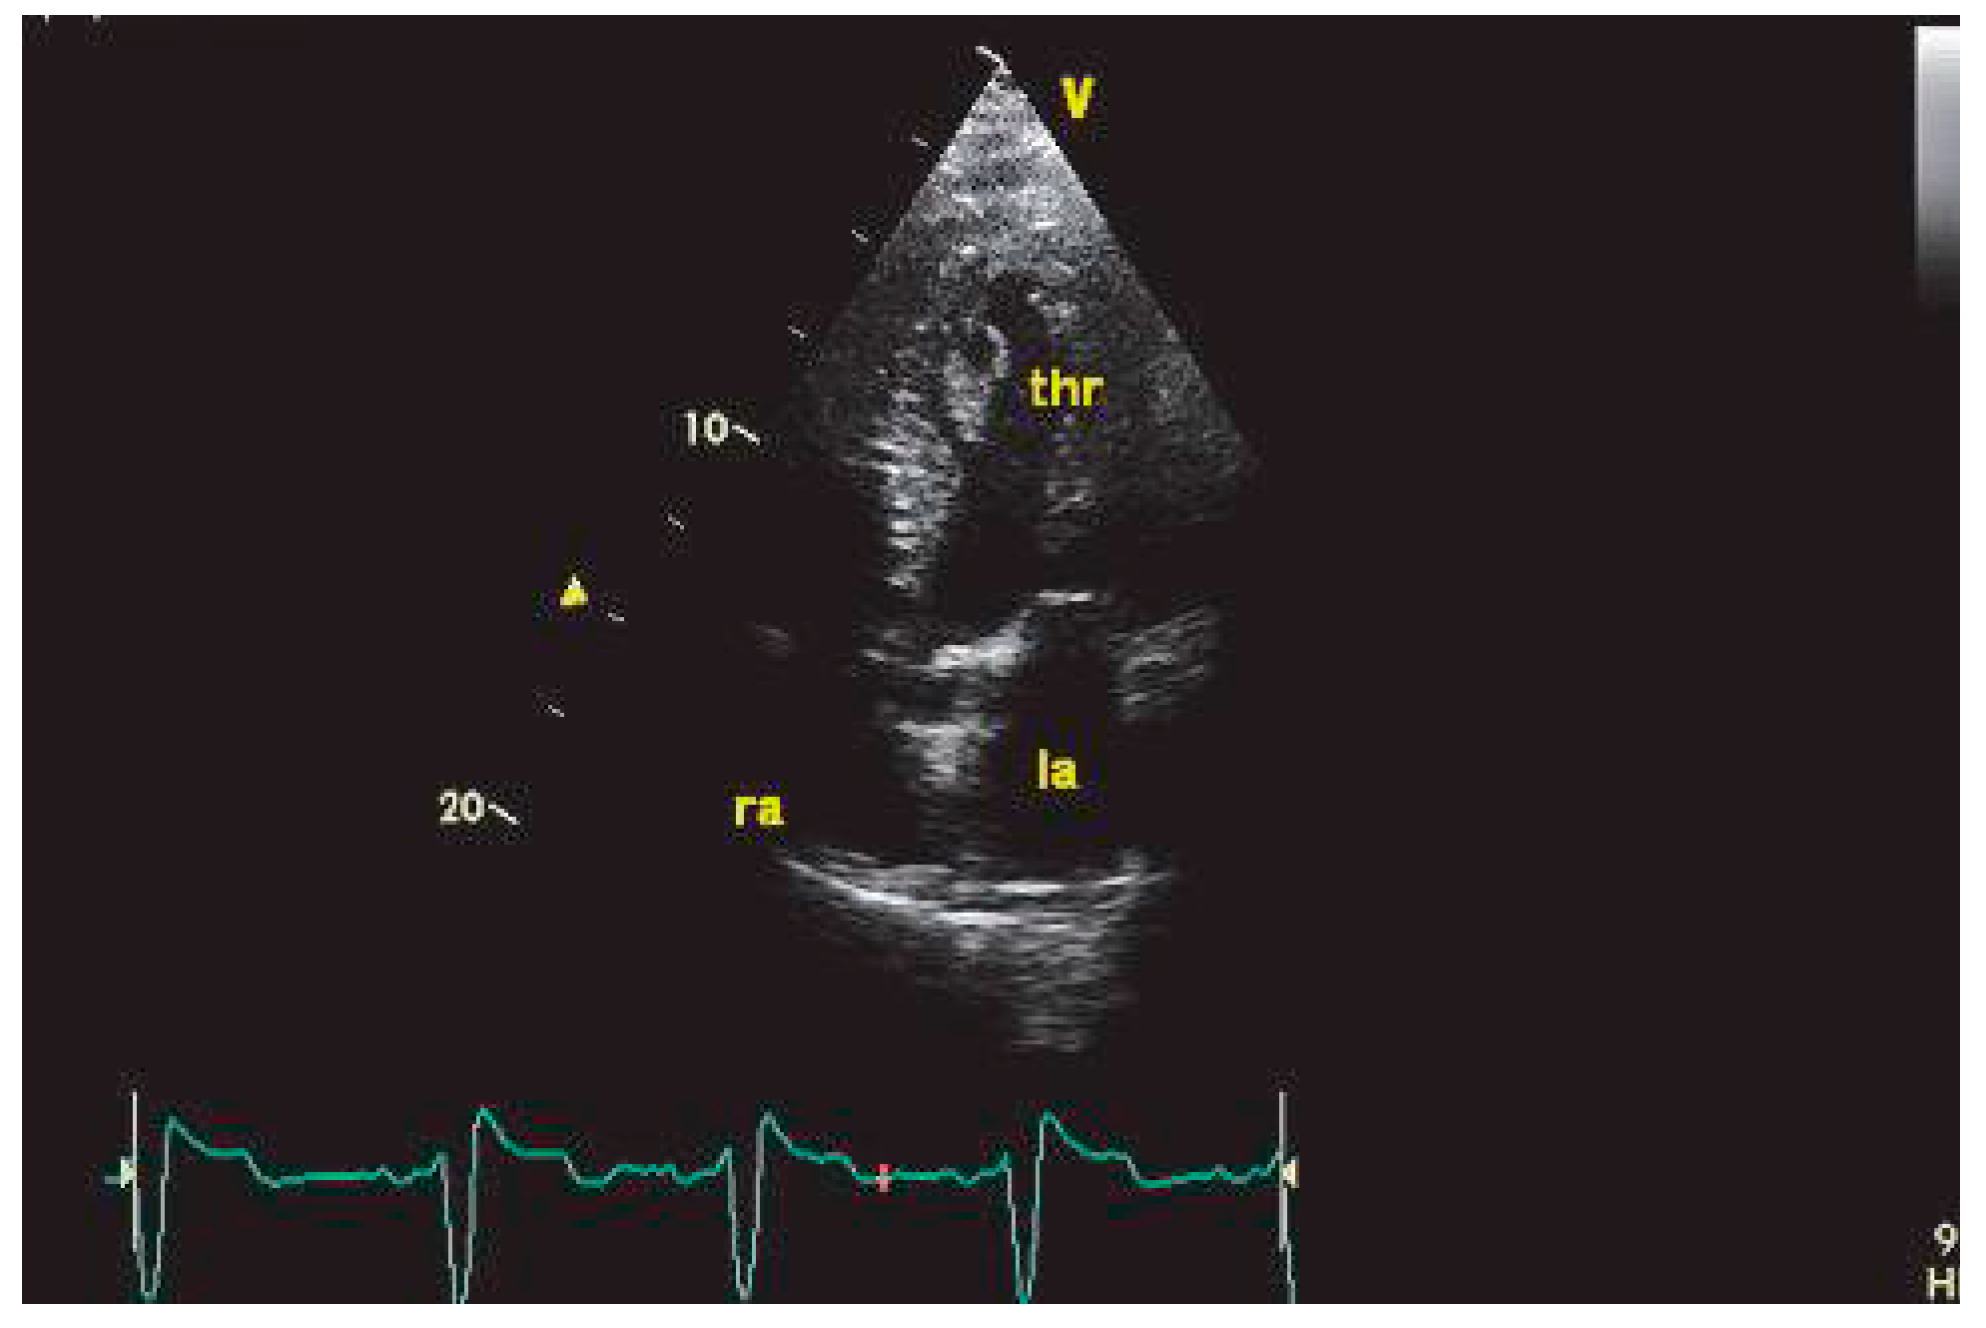

Thrombus et dysfonction systolique ventriculaire gauche ischémique et non ischémique

L’AIC complique un infarctus du myocarde (IDM) dans 2 à 4% des cas [27]. La thrombose ventriculaire gauche (VG) est habituellement précoce, survenant dans la première semaine suivant l’IDM. Le siège électif est l’apex VG, en regard d’une zone akinétique ou dyskinétique, ou au sein d’un anévrisme (Figure 2). Cette localisation élective explique la performance diagnostique élevée d’ETT. La présence d’un thrombus VG à la phase aiguë d’un IDM multiplie par 5 le risque embolique [28].

Dans les cardiopathies non ischémiques, la prévalence de la thrombose VG est élevée, en particulier lorsque la FEVG est inférieure à 45% [29]. Dans les cardiopathies dilatées évoluées, les fréquences rapportées de thrombose VG se situent entre 11 et 44%. L’incidence des événements emboliques est évaluée entre 1.4 et 12.0% par an dans cette population [29,30]. Dans la série de Sharma [31] comportant 144 patients consécutifs avec FEVG inférieure ou égale à 35% examinés par ETT dans le cadre d’un programme d’évaluation prétransplantation cardiaque, 19% avaient un thrombus VG. Les patients avec thrombus VG avaient un diamètre télédiastolique VG significativement plus important, une fréquence plus élevée de cardiopathie ischémique et d’anévrisme antéro-apical et une FEVG tendant à être plus basse (17.5 ± 5.5% versus 20.0 ± 6.9%, p = 0.07). Il n’y avait pas de différence significative en termes de fréquence des événements emboliques, une embolie artérielle étant survenue chez 17.9% des patients ayant un thrombus VG et 11.2% des patients n’ayant pas de thrombus VG (p = 0.35), au cours d’un suivi moyen de 27.6 ± 14.9 mois. Les seuls facteurs prédictifs des accidents emboliques en analyse multivariée étaient la présence d’une cardiopathie ischémique (odds ratio 3.79, intervalle de confiance à 95%: 1.13–12.64, p = 0.03) et une FEVG basse (odds ratio 0.91, intervalle de confiance à 95%: 0.82–1.00, p = 0.04).

Figure 2. Thrombus mobile du VG chez un patient hospitalisé pour AIC et porteur d’une séquelle apicale, visualisé en ETT par la fenêtre apicale.